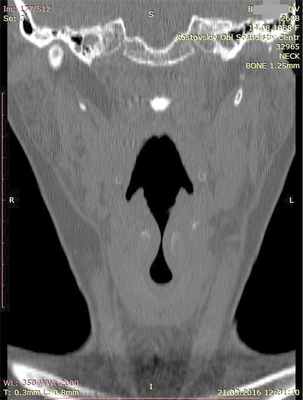

На спиральной компьютерной томографии (СКТ) гортани отмечается асимметрия грушевидных синусов, левый синус сглажен. Определяется отек мягких тканей гортани на уровне подскладкового пространства. Просвет гортани сужен до 2 мм на протяжении 6,5 мм (рис. 2). Деструктивных изменений хрящей гортани не выявлено. На СКТ органов грудной клетки признаков структурных изменений не наблюдается.

Рис. 2. СКТ гортани пациентки Б. в коронарной проекции. Просвет подскладкового пространства сужен до 2 мм на протяжении 6,5 мм.